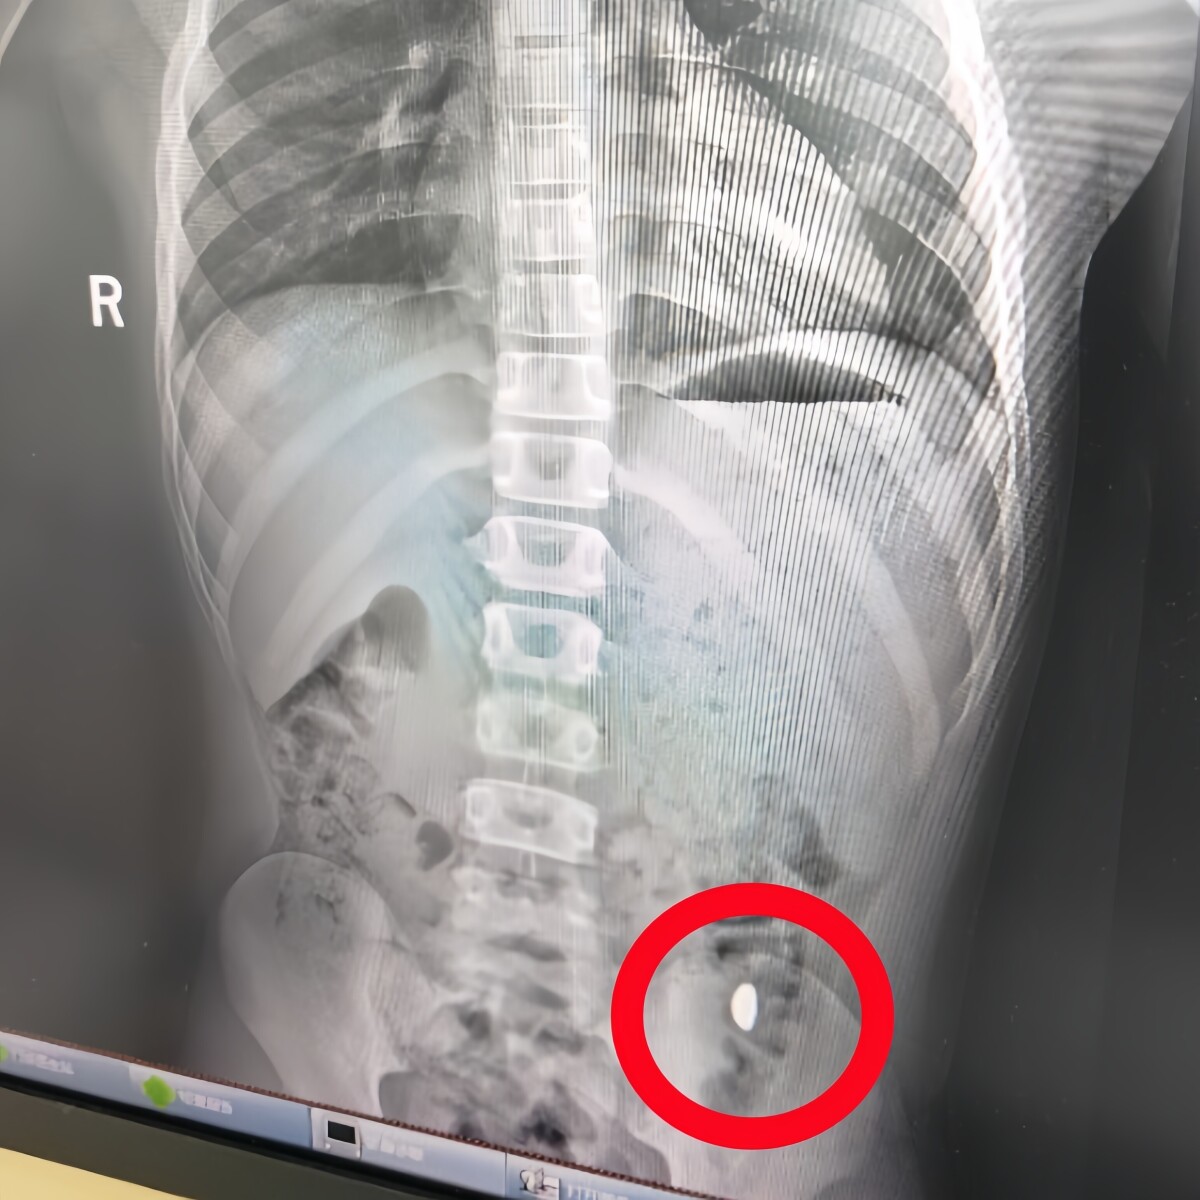

11歳男児が金の粒を飲み込む、母親「外でうんちしちゃだめ」―中国

27日、九派新聞は、子どもが10グラムの金の粒を飲み込み、母親が外出先での排便を禁止するトラブルがあったことを報じた。